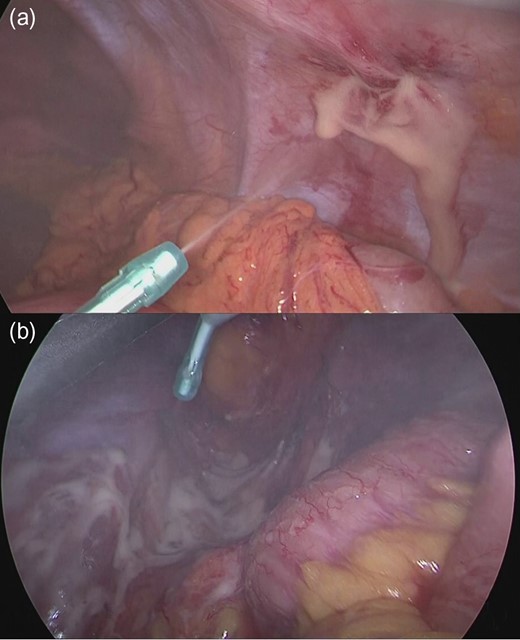

The spray-type anti-adhesion barrier (Ad Spray type L®(TERUMO Corp, Tokyo, Japan)) consists of a dissolution kit and a Sprayer Kit (Fig. 1a), and the kit is assembled after combining the two drugs. The regulator is then connected to a compressed air supply for use (Fig. 1b). The nozzle is 334 mm long, and the angle of the tip is adjustable from 0-90 degrees, and the rotation of the shaft is 360 degrees. However, while it is difficult to secure the working space by fine-tuning the angle and rotation of the tip, it is possible to easily apply the spray to the desired part. In addition, since gelation after application requires about 10 seconds, some degree of viscosity is obtained, and it is useful to maintain the adhesion barrier at the area of the curvature and the damaged peritoneal portion of the abdominal wall side. We apply the barrier to the port insertion area from within the peritoneal cavity (Fig. 2a) and the peeling surface at the small incision. In particular, the peeling surface is widely used, such as the pelvic floor at the time of milestone surgery, and it is difficult to use the sheet type anti-adhesion barrier in the Hartmann operation (Fig. 2b). In order for the barrier to remain in the target region, this preparation must remain viscous after application. The area of the coating is similar to the sheet type.

(a) Apply the barrier to the port insertion area. (b) Spraying the peeled surface of pelvic cavity in the Hartmann operation.